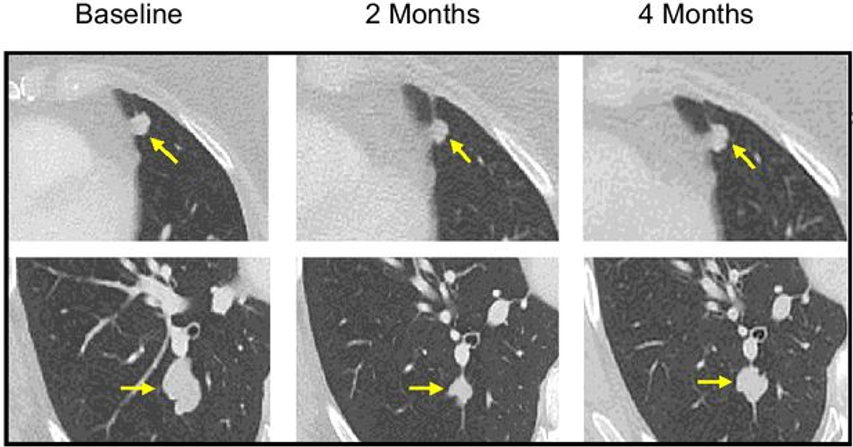

随着技术水平不断提升,人们对癌症的探索逐渐深入,癌症治疗的策略也在不断改变。而近年来,利用免疫系统来对抗癌细胞被发现是一种非常具有潜力的治疗方式。其中肿瘤浸润淋巴细胞(TIL)疗法已成为一种有前途的实体瘤治疗策略,并在2024年被批准用于既往接受过免疫检查点抑制剂和BRAF/MEK靶向治疗(如适用)的晚期黑色素瘤患者。